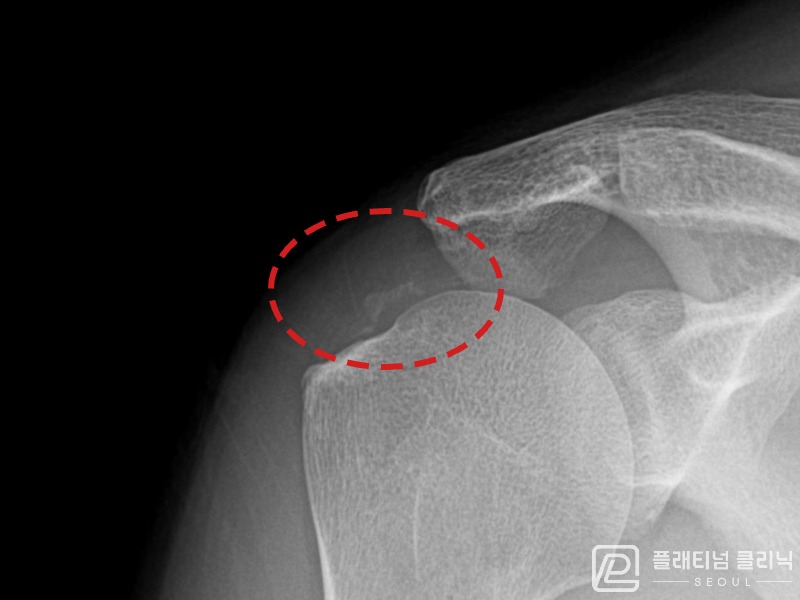

[촬영시기:21.11.04~21.11.09]

[석회분쇄흡입술] 우측 어깨 극심한 야간 통증으로 수면이 불가능해진 50대 여성 환자로, X-ray에서 우측 극상근건 내 석회 침착이 확인되어 석회분쇄흡입술을 시행하였습니다.